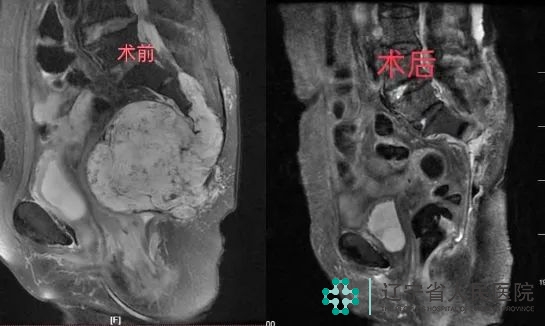

术前、术后MRI对比

整个手术持续大约4小时,非常顺利,术中有效地控制了出血量,在肿瘤完整切除的同时又保护了患者的大小便功能,术后病理结果确诊肿瘤为脊索瘤。